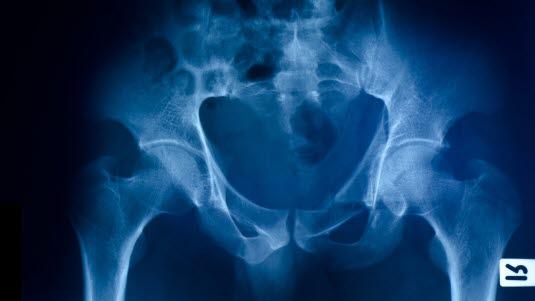

Femoralisnerven kan skades ved bekkenbrudd, lårbeinsbrudd og skader hvor hofta kommer ut av ledd. Skade av denne nerven er med andre ord vanligvis en følgeskade etter kraftige traumer, som for eksempel ved bilulykker og lignende. Tilstanden kan også være en komplikasjon til barnefødsel og prosedyrer som innsetting av hofteprotese, buk- eller bekkenkirurgi eller laparoskopi, lymfeknutebiopsi, blokkade av femoralnerven og punksjon av lårpulsåren (arteria femoralis).